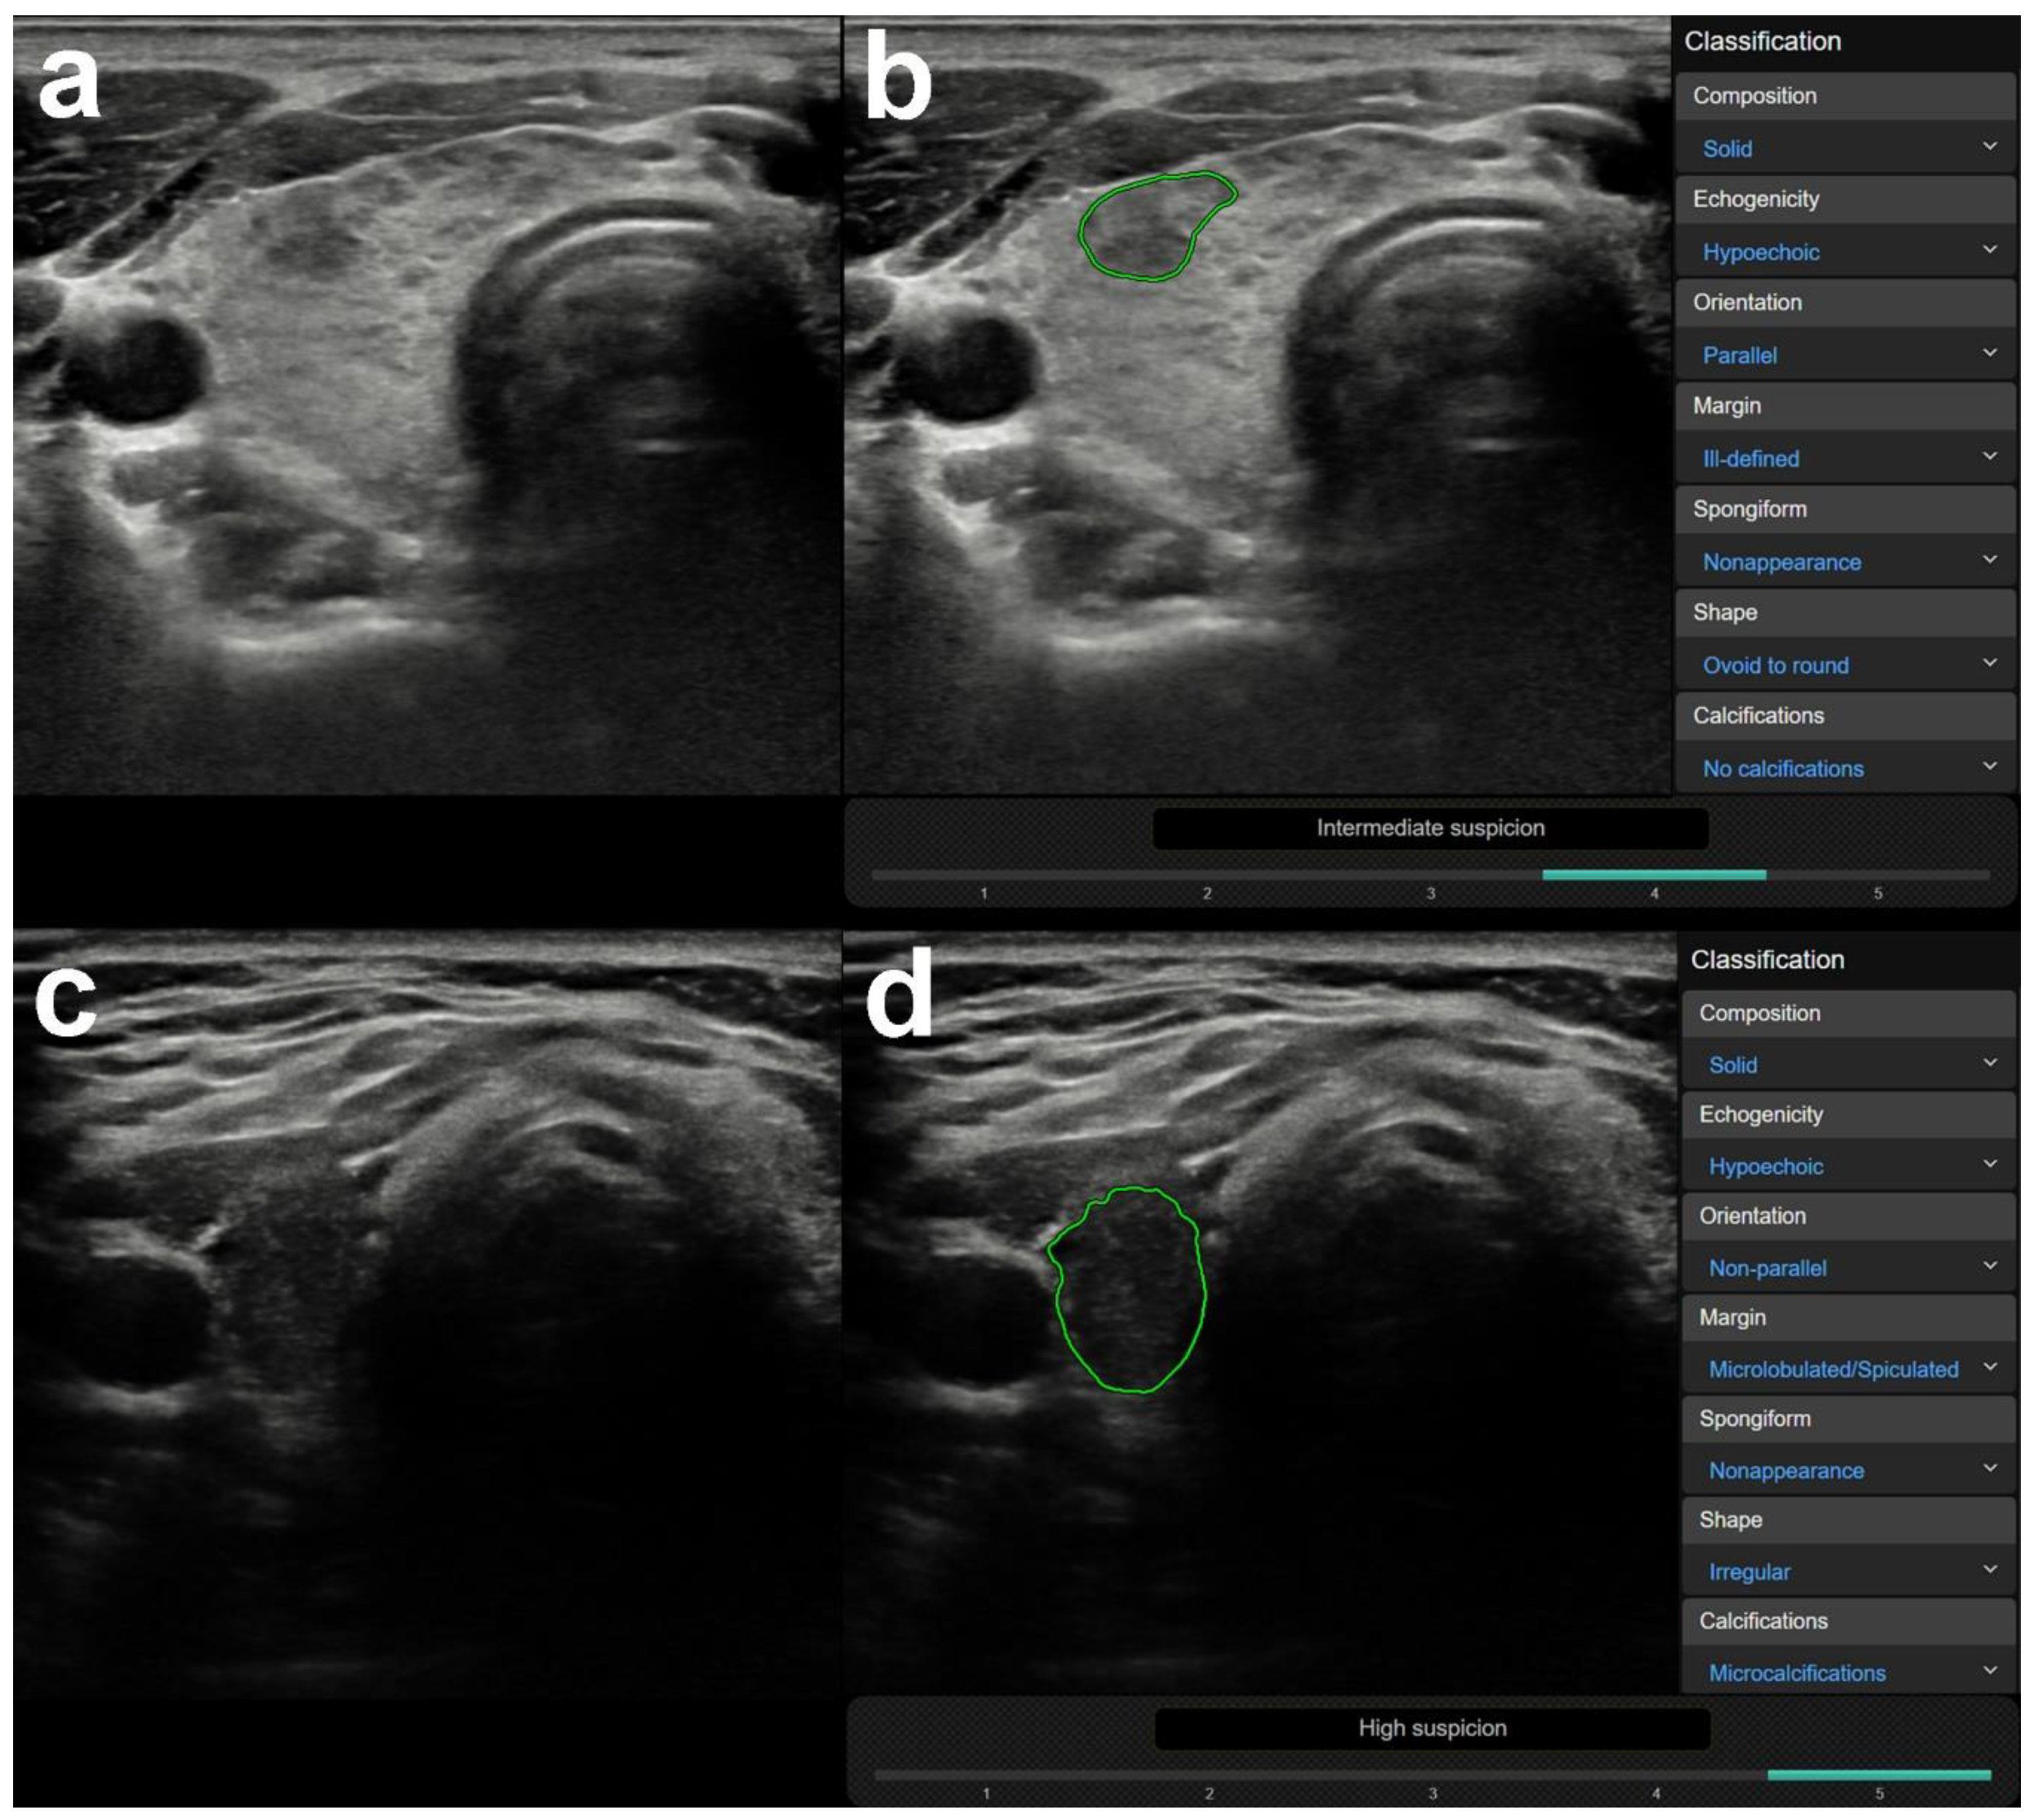

3.1. US Features or Entities Associated with CAD System Misdiagnosis Including Mimicking Lesions